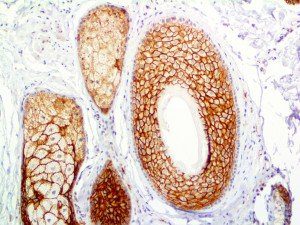

The first cytokines released are interleukin 1β (IL-1β) and tumor necrosis factor-α (TNF-α), which attract a variety of circulating white blood cells (WBCs) to the infection site, including neutrophils, monocytes, macrophages, and natural killer (NK) cells. This response, along with the antipathogenic chemicals released by these cells (i.e., complement), comprise the innate immune response. These cells directly attack the invading pathogen and also release additional cytokines, chief among them interleukin-1 and 6 (IL-6). IL-6 is essential for invoking the adaptive immune response, which calls T-cells, B-cells, and T helper (Th) cells to the infection site. IL-6 also stimulates further recruitment, proliferation and activation of macrophages.

This activation induces inflammatory monocytes to highly express IL-6, starting a localized and then systemic cascade effect that results in hyperproduction of IL-6, which accelerates the inflammatory process. Because IL-6 also increases vascular permeability, excessive levels cause blood vessels to become very leaky. This, along with clotting factors released from vascular endothelial cells, stimulates the coagulation cascade, resulting in microthrombosis (tiny clots), which leads to ischemia and tissue death of the kidney, intestines, heart, liver, brain and extremities.